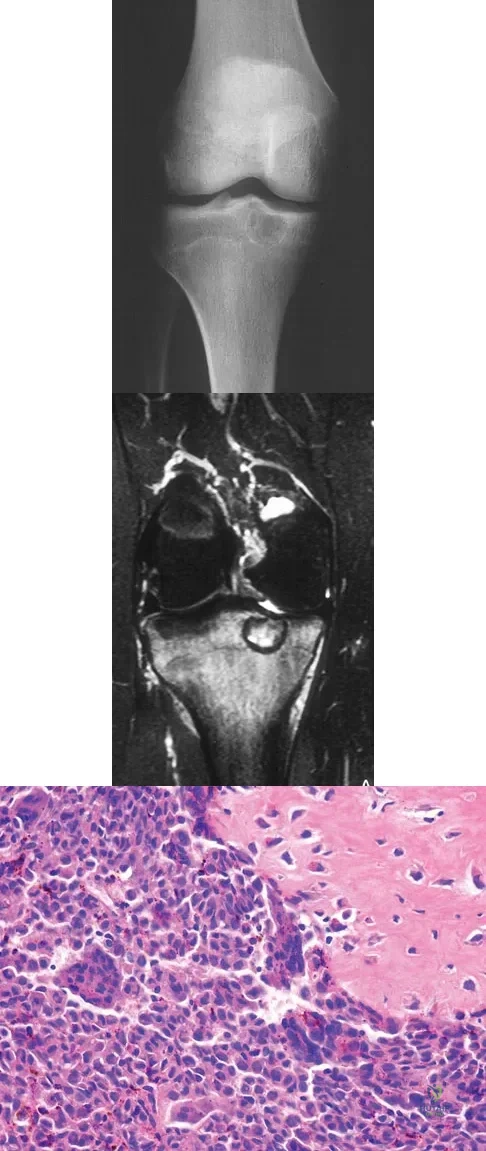

A 15-year-old girl reports a 6-month history of activity-related knee pain and swelling. A radiograph, MRI scan, and biopsy specimen are shown in Figures 21a through 21c. What is the most likely diagnosis?

The epiphyseal location on the radiograph and MRI scan and the histologic findings of polyhedral cells separated by a chondroid matrix with pericellular, lattice-like "chicken wire" calcification all suggest chondroblastoma. Although giant cell tumors of bone typically occupy an epiphyseal location, they are rare in children and when present are often metaphyseal in skeletally immature patients. Enchondromas and osteoblastomas are generally metaphyseal and, along with giant cell tumors, have very different histology than seen here. Chondromyxoid fibromas are typically metaphyseal in location. Huvos AG: Bone Tumors: Diagnosis, Treatment, and Prognosis. Philadelphia, PA, WB Saunders, 1991, pp 295-313.